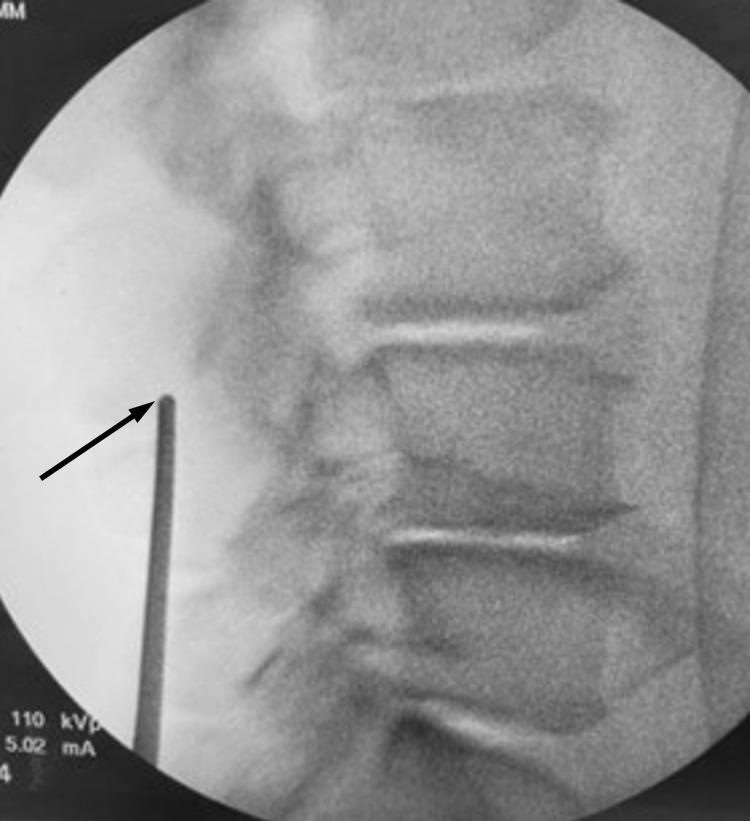

Prospective evaluation of radiographic fusion outcomes in patients receiving instrumented posterior arthrodesis of the lumbar spine using a minimally invasive interspinous fixation device.

All patients (n = 110) from a single US physician's practice who received instrumented posterior arthrodesis of the lumbar spine with a minimally invasive interspinous fixation device in the calendar year 2020 were invited to return for a follow-up CT scan to radiographically assess fusion. Forty-three patients, representing 69 total treated levels, consented to participate and received a lumbar CT scan at a mean of 459 days post-surgery (177 to 652). The interspinous/interlaminar fusion was assessed by 3 independent radiologists using a novel grading scale. Spinous process fractures were also assessed.

92.8% of the assessed levels were considered fused. There were no intraoperative spinous process fractures. There were 4 spinous process fractures (5.8%) identified on CT imaging, all of which were asymptomatic and healed without subsequent intervention. There were no instances of device mechanical failure or device-related reoperation.

Instrumented posterior arthrodesis of the lumbar spine using a minimally invasive interspinous fixation device provides clinically meaningful fusion rates with no reoperations and a low risk of spinous process fracture or other device-related complications.